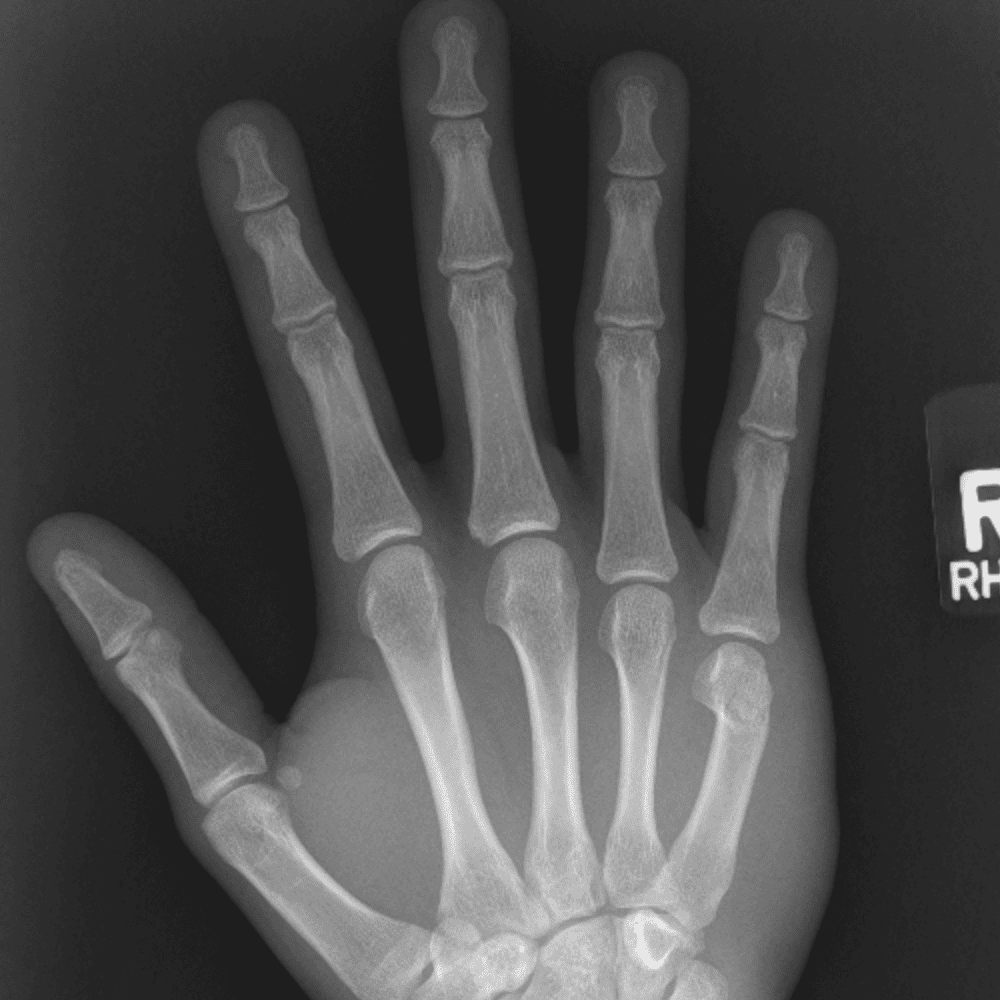

Simulates call by including subtle or difficult cases and some normals.

30 cases